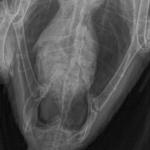

Koalla88 Опубликовано 23 февраля, 2016 Автор #8 Опубликовано 23 февраля, 2016 С огромным трудом сделали рентген, птицу расположить в позе Христа не получилось, к сожалению. Так же в клинике предложили переделать под ингаляционным наркозом, насколько он опасен для птиц? Файлы рентгена прилагаю.

KamaRo Опубликовано 23 февраля, 2016 #11 Опубликовано 23 февраля, 2016 Рентген сможет прочитать Зося при условии если он читабельный,напишите ей в личку http://www.mybirds.ru/forums/index.php?showuser=4292 Вы анализы какие нибудь сдавали? рентген - это хорошо, но и анализы нужны.